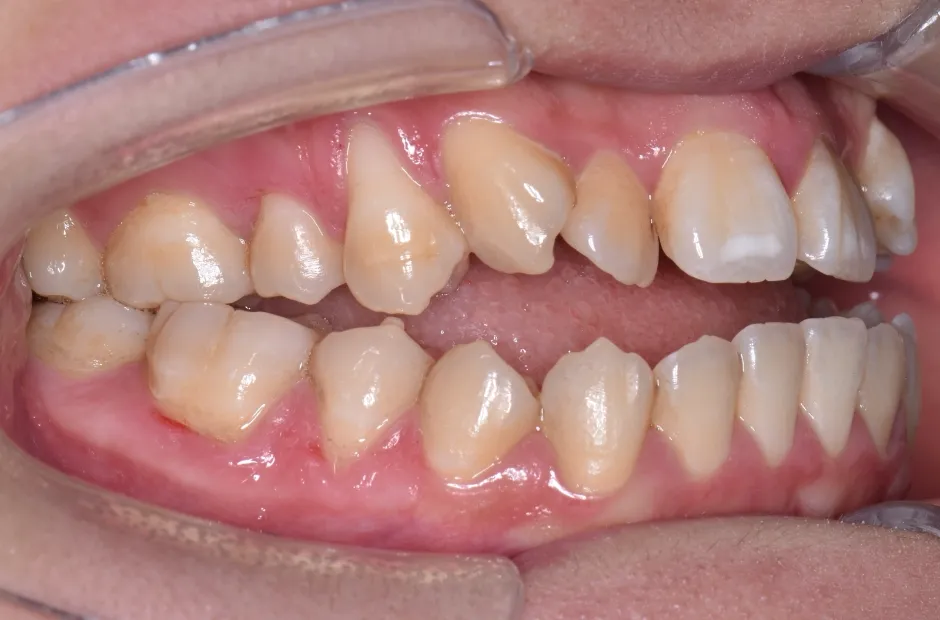

叢生

| 診断名・主訴 | 叢生 |

|---|---|

| 年齢・性別 | 43歳・女性 |

| 治療期間・回数 | 2年7か月 27回 |

| 治療に用いた主な装置 | 舌側矯正 |

| 抜歯部位 | 両顎4,4 |

| 治療費 | 100万円(税抜) |

| リスク・副作用 | 装置による違和感・疼痛・歯肉退縮・歯根吸収・虫歯のリスクなど |